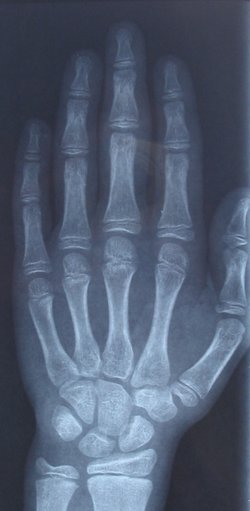

Radiografia

Una radiografia és una prova diagnòstica que utilitza els raigs X per veure l’interior del cos. Sobretot s’utilitza per examinar ossos i pulmons.

La zona del cos a irradiar es col·loca davant d’una placa o pel·lícula. Quan s’irradia una zona del cos, aquestes radiacions passen a través amb diferent intensitat, depenent de la densitat de la zona. Les estructures més denses, com els ossos, es veuen de color blanc, l’aire de color negre, i la resta d’estructures en diferents tonalitats de grisos en funció de la seva densitat (vegeu la figura).

Les seves principals utilitats són el diagnòstic de fractures d’ossos, càries, pedres al ronyó o pneumònies.

Els raigs X són radiacions ionitzants que traspassen la matèria.

Per a la realització d’una radiografia, la persona usuària s’ha de col·locar entre la font de raigs X i el detector. La posició dependrà de la zona del cos a irradiar. És convenient tenir la zona sense roba, i no es pot portar cap objecte metàl·lic. En el moment d’efectuar la radiografia cal estar completament quiet i no respirar. Cal tenir especial precaució en nens, adolescents i dones embarassades.